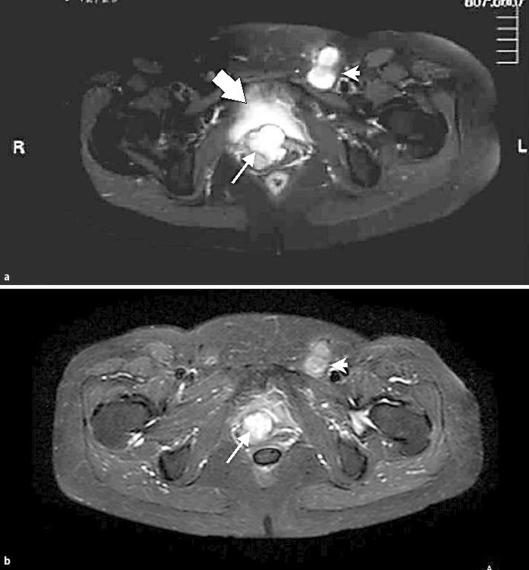

Advances in treatment have not recently been reported in rare primary vaginal adenocarcinomas. A 56-year-old woman with a chronic vaginal cyst and possible in utero diethylstilbestrol exposure presented with postmenopausal bleeding. Biopsy of the vagina revealed high-grade papillary serous adenocarcinoma. MRI showed a 6-cm vaginal tumor and 3-cm left inguinal lymph node with metastasis. The patient initially received concurrent cisplatin and radiation. She then received high-dose-rate brachytherapy for further local control. Brachytherapy following external beam radiation with concurrent cisplatin led to clinically undetectable cancer at 24 months with minimal side effects.